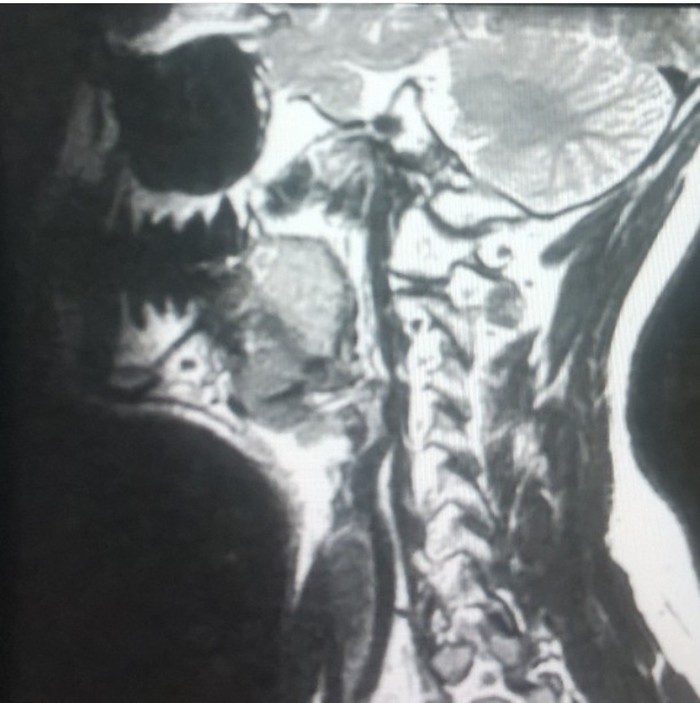

1. Бойцы Mortal Combat

Артефакты от металлических конструкций на зубах.